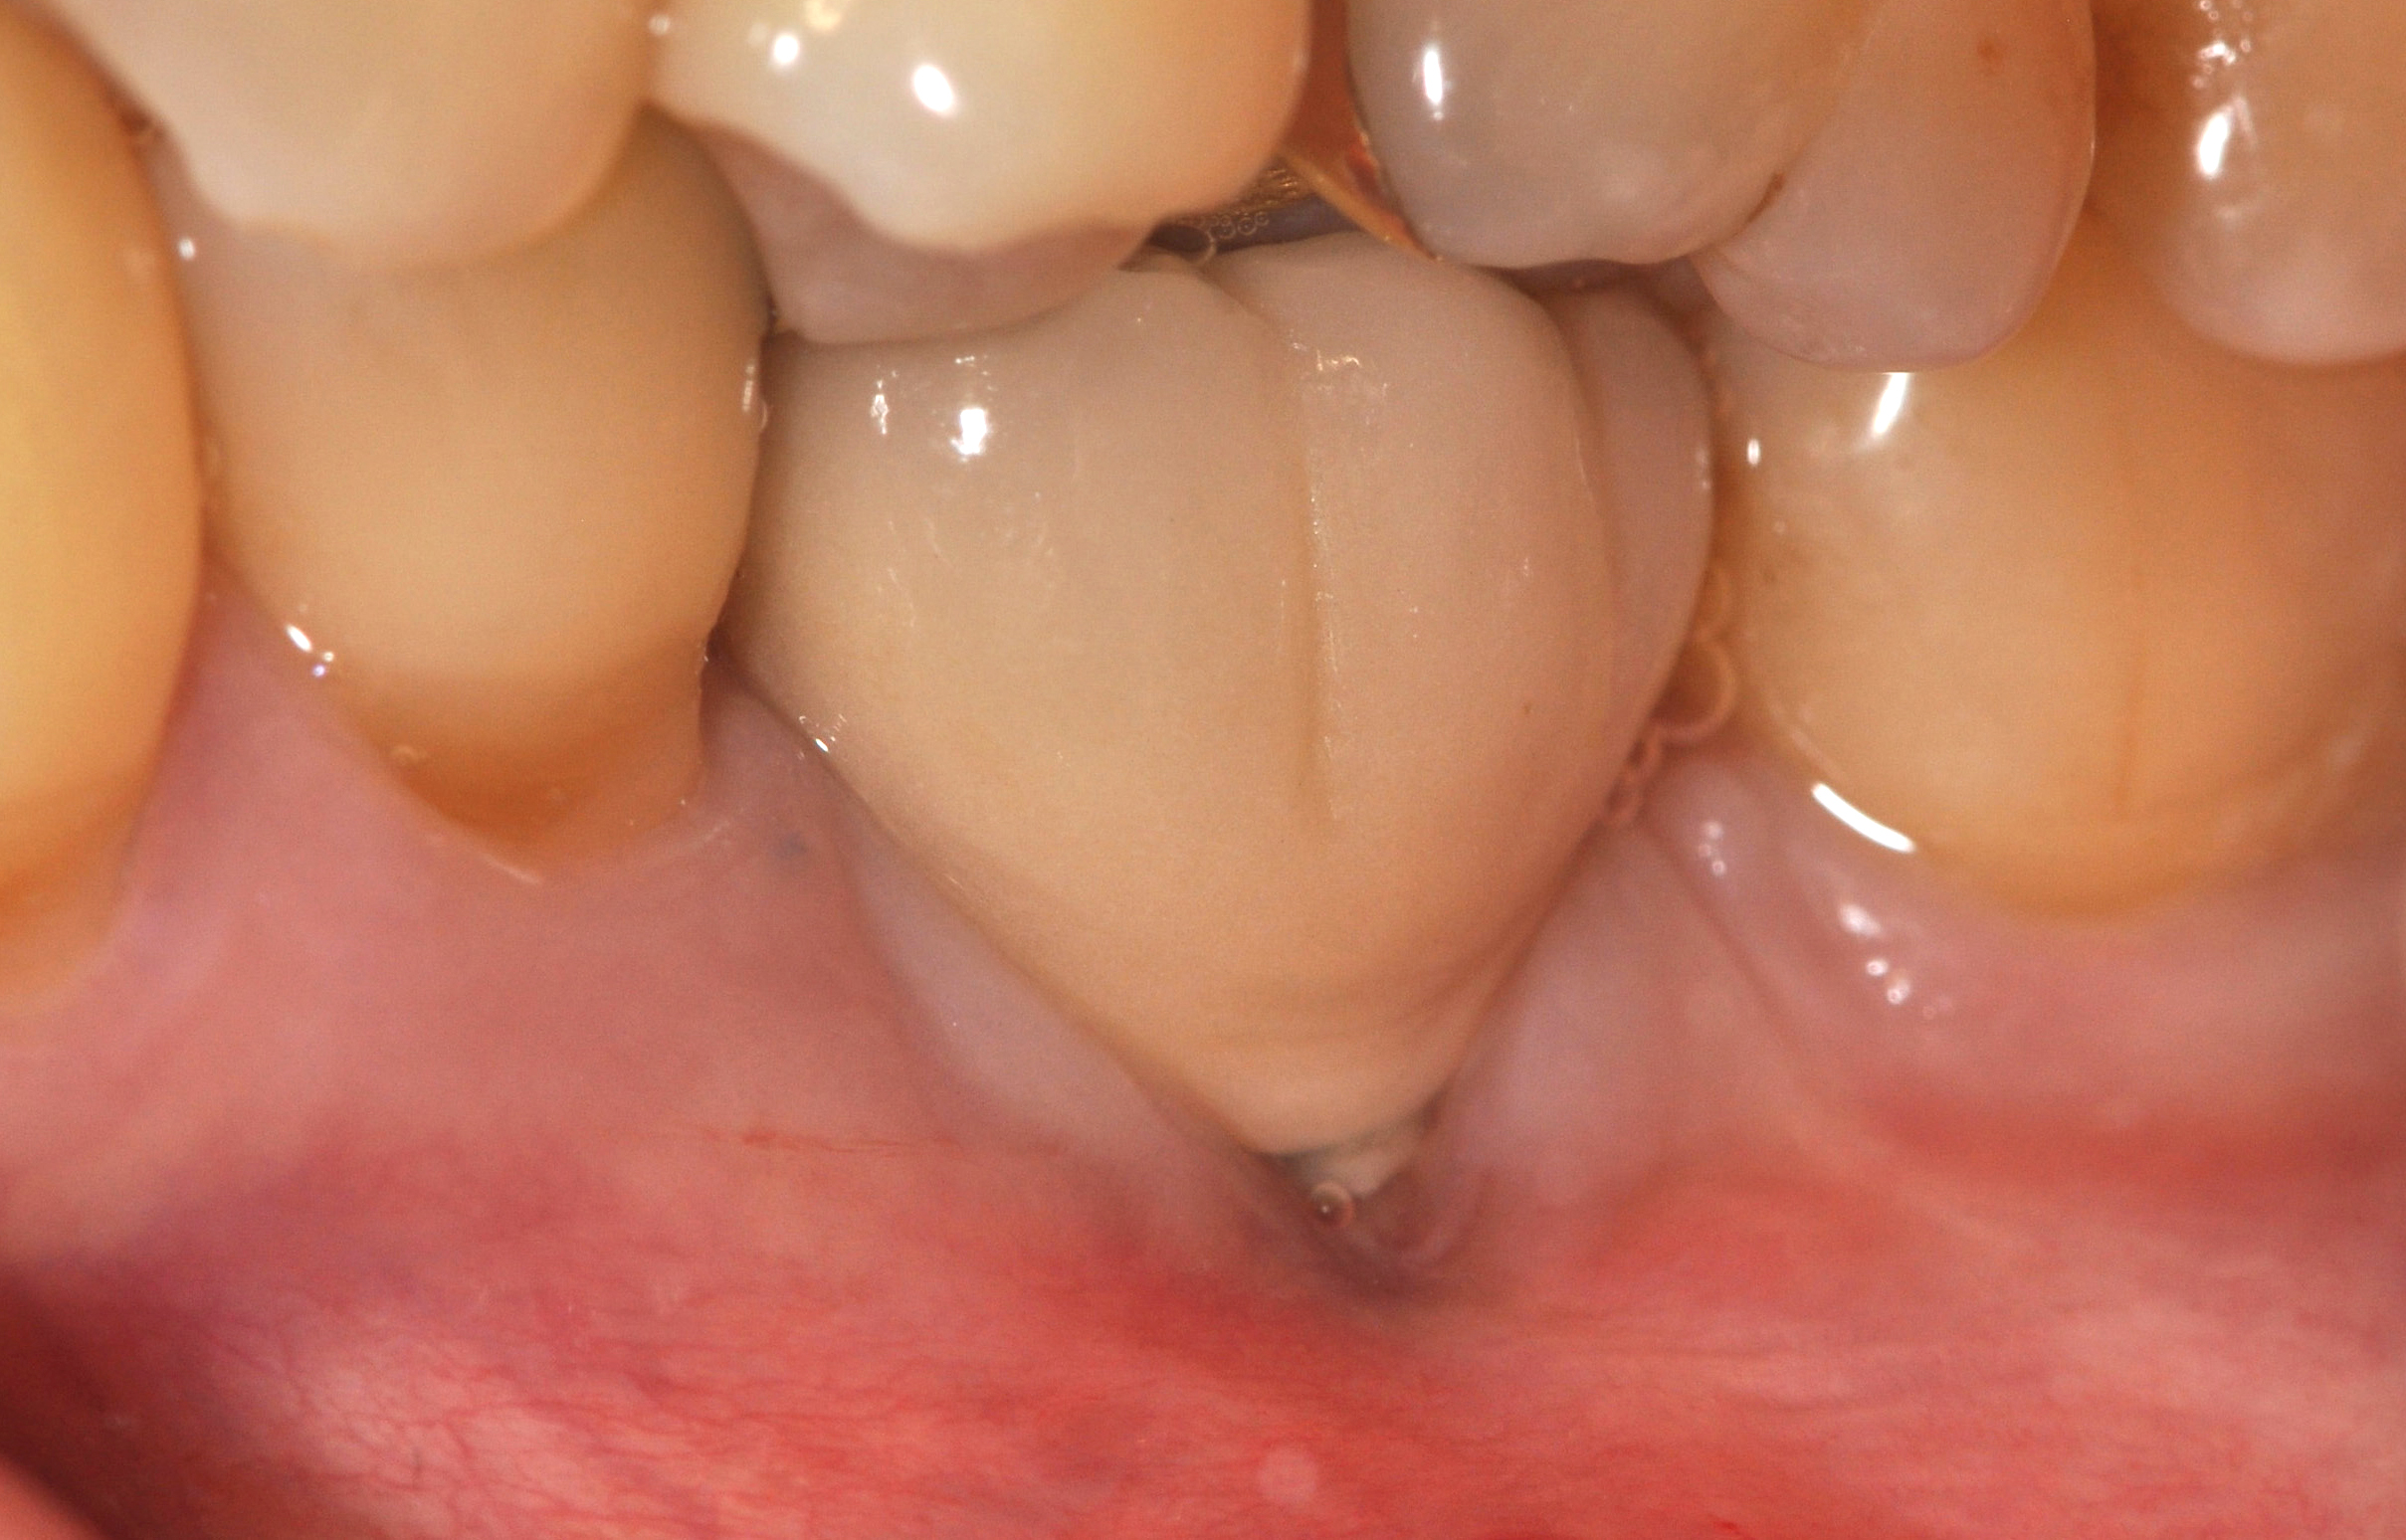

Problem: The implant is placed too facial with significant recession on the midfacial aspect of the abutment and/or crown; the implant is healthy and the patient has a high smile line with an intermediate to thick periodontal phenotype (Figure 1 and Figure 2).17-19

Fig 1. Midfacial recession can affect the esthetics of a smile and lead to an unsatisfactory outcome.

Fig 2. The cause for midfacial recession is excessive labial implant placement. Secondary to poor placement is overcontouring of the implant abutment.